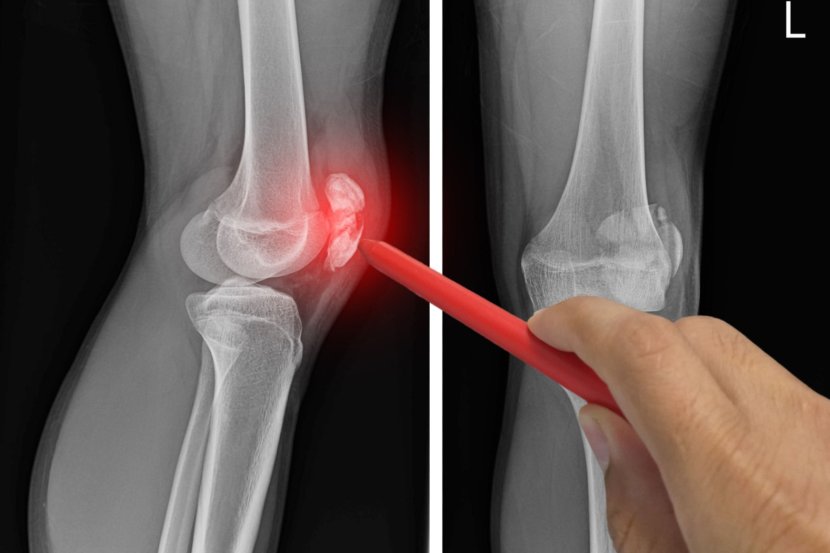

Povreda ili oštećenje meniskusa može da bude rezultat naglog uvrtanja ili rotacije kolena, naprezanje tokom čučnja, savijanja ili podizanja teških predmeta ili jakog udarca usled borbe ili druge sportske aktivnosti. Stepen povrede može da varira od naprezanja do delimičnog ili potpunog kidanja meniskusa. Lečenje simptoma povrede meniskusa varira u zavisnosti od stepena povrede i može da bude konzervativno kao što je odmor i "zaleđivanje" hladnim oblogama do drastičnijih intervencija kao što je operacija.

Meniskus je amortizer u obliku polumeseca u kolenu koji se nalazi između butne kosti (budrene kosti) i tibije (golenice). Svako koleno ima dva meniskusa. Jedan je na medijalnoj strani, bliži drugom kolenu, a drugi na bočnoj strani, najbliži spoljašnjoj strani noge. Tokom aktivnosti na stopalima, hrskavica meniskusa ublažava habanje okolne zglobne hrskavice, koja je zaštitni sloj na krajevima kostiju.

Pokidani meniskus je uobičajena povreda u kojoj je oštećena hrskavica koja čini jastuk meniskusa i narušen je integritet površine. Kao i kod većine povreda meniskusa, meniskus se može pokidati tokom sportskih aktivnosti poput trčanja i brzog okretanja. Kod starijih osoba, degeneracija hrskavice u kolenu, poznata i kao osteoartritis, može da oslabi meniskus tako da se pokida, čak i ako je malo sportske aktivnosti ili naprezanja. Poput pukotine u ledu, pukotina meniskusa u kolenu može da se širi u mnogo različitih pravaca.

Svaka aktivnost, koja uzrokuje nasilno uvijanje ili rotiranje kolena, posebno kada se punom težinom oslanjamo na njega, može da dovede do pucanja meniskusa. Ta povreda izaziva bol, otok i ukočenost. Takođe, čovek može da oseti blokadu pokretljivosti kolena i teško da može da ispruži  koleno. Konzervativni tretman, kao što su mirovanje, led i lekovi, ponekad je dovoljan da ublaži bol pokidanog meniskusa i da povreda vremenom zaceli sama od sebe. U drugim slučajevima, međutim, povreda meniskusa zahteva operaciju. Ako se sumnja na povredu meniskusa, ortoped može da traži rendgenske snimke i magnetnu rezonancu kako bi potvrdio dijagnozu i dodatno procenio stanje zgloba kolena.